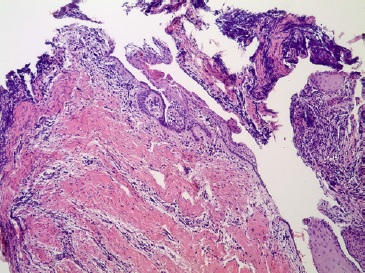

O exame microscópico revelou fragmento de cápsula cística parcialmente revestida por epitélio estratificado pavimentoso não ceratinizado. A cápsula era constituída de tecido conjuntivo fibroso celularizado com vasos e infiltrado inflamatório mononuclear. Focos de calcificação distrófica também foram observados (Figuras 9 e 10). As características clínicas, imagiológicas e histopatológicas, foram compatíveis com o diagnóstico de cisto radicular.

Figura 9 Fotomicrografia de corte histológico corado em hematoxilina e eosina, mostrando fragmento de cápsula cística revestida por epitélio estratificado pavimentoso não ceratinizado - 100x

Figura 10 Fotomicrografia de corte histológico corado em hematoxilina e eosina, mostrando infiltrado inflamatório mononuclear e áreas de calcificação distrófica na cápsula cística, bem como seu revestimento por epitélio estratificado pavimentoso não ceratinizado - 100x.